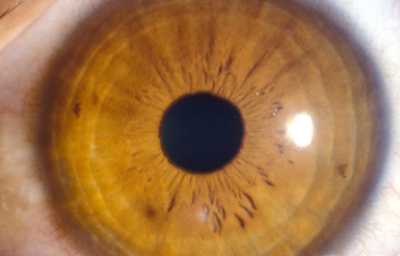

A los 6 meses se realiza angiografía del Iris que muestra en las fases tardías la existencia de exudación en el estroma superior, pupila de 3.0mm normoreactiva (Foto No 6 y 7), y se formula Pred F nuevamente cada 2 horas durante 1 mes con reducción progresiva hasta el siguiente control.

A los 18 meses se realiza una segunda angiografía del Iris,(Foto No 8 ) mostrando ausencia de exudación; la córnea es trasparente con leucoma tenue superior, despigmentación del estroma iridiano en 360o con pupila de 3.0mm normoreactiva (Foto No 9), opacidad subcapsular anterior en el cristalino y Refracción: Plano ( -1.25 x 180a) 0.80. Se sugiere mantener Pred F 1 gota cada 5 días.

Foto 6 Angiografìa a los 6 meses con Exudación en el Iris

Foto 7 Foto del OD a los 6 meses

mostrando edema a las 12 y despigmentación del Iris en 360o

Foto 8 A los 18 meses, Angiografía sin exudación, solo despigmentacióno

Foto 9 Foto a los 18 meses post tratamiento

Ultimo control a los 28 meses del accidente, con ojo OD tranquilo TO: 10, córnea trasparente con leucoma superior residual, despigmentación del Iris en 300o con pupila normoreactiva y opacidad anterior en el cristalino. Agudeza Visual mejor corregida 0.80